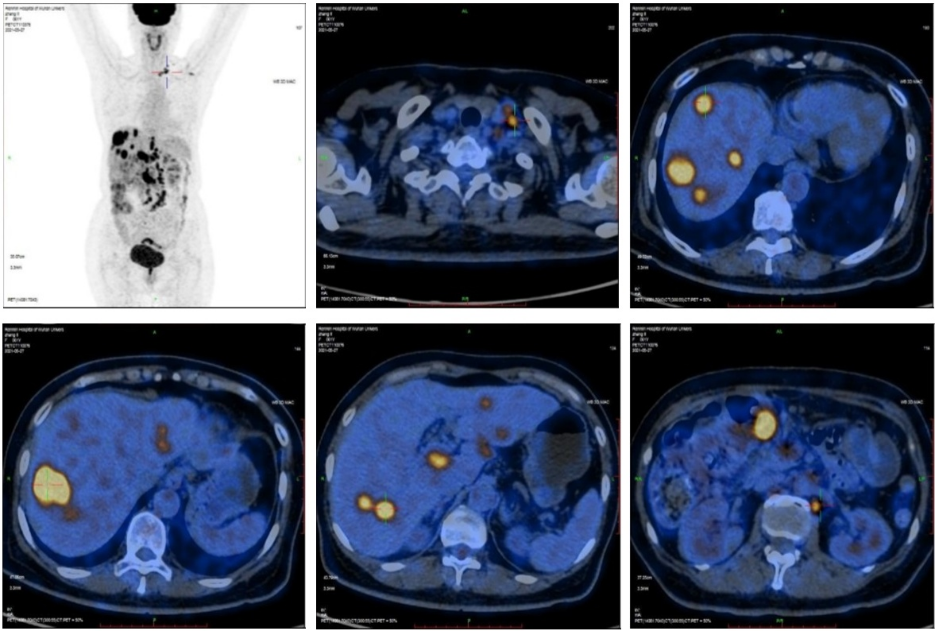

2021-5-27 我院全身PET/CT示:横结肠近结肠肝曲肠壁增厚,代谢增高;肝内多发团块、结节灶,代谢增高;左颈部Ⅴ区、左锁骨上区、左侧膈肌脚内侧、肝门区、胰腺后方、横结肠周围及腹膜后区多发肿大淋巴结,代谢增高;上述考虑恶性病变,结肠癌伴肝脏、淋巴结转移。

PET/CT影像: